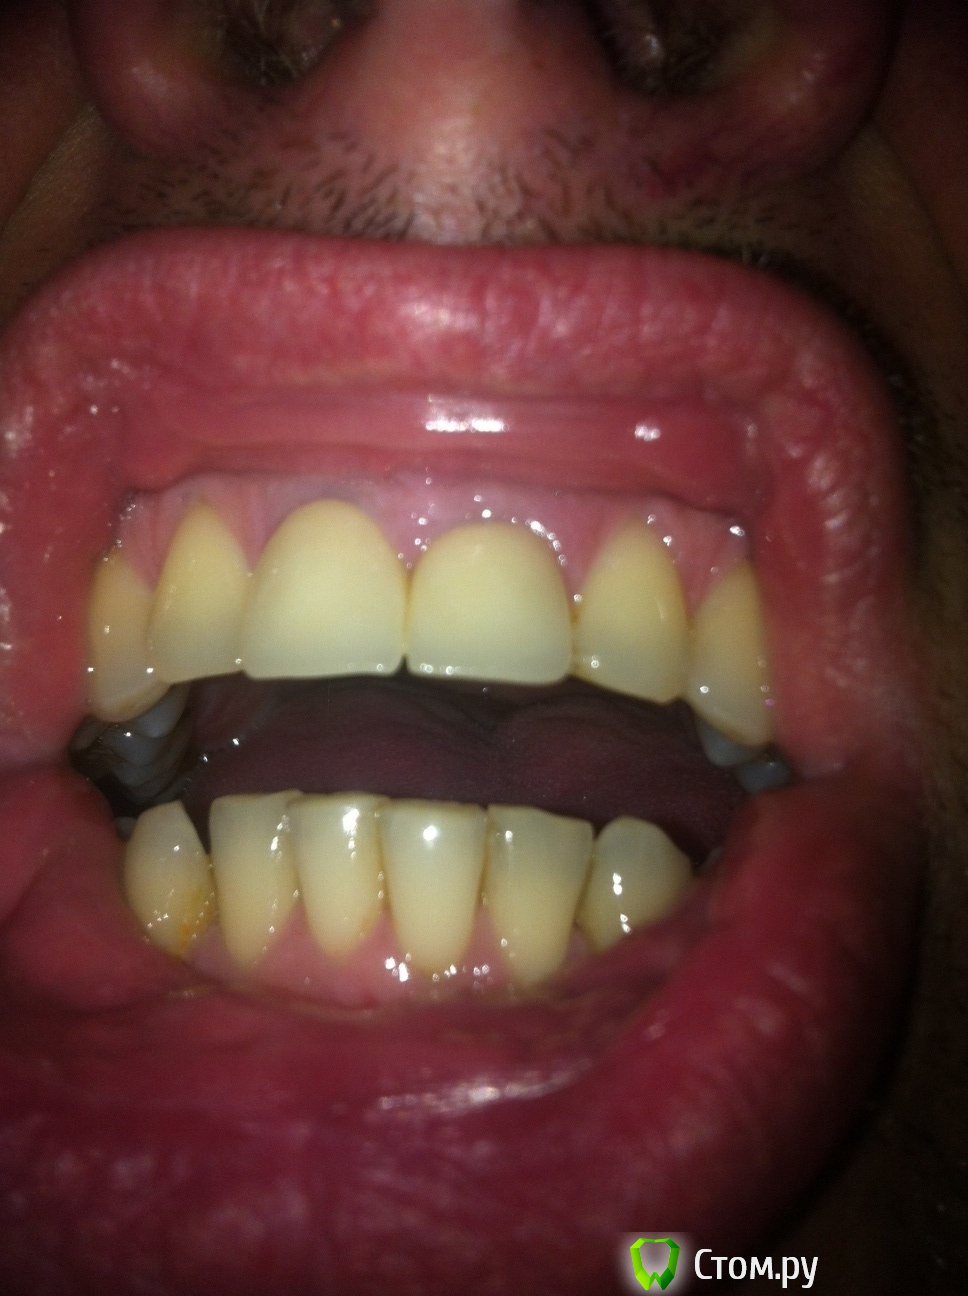

red_butler Опубликовано 12 декабря, 2013 Поделиться Опубликовано 12 декабря, 2013 Покажите фото сомкнутых зубов, прямо и сбоку. Лечить и повторно протезировать Ссылка на комментарий

alexjuk1 Опубликовано 12 декабря, 2013 Автор Поделиться Опубликовано 12 декабря, 2013 Это до удаленя вкладок http://s019.radikal.ru/i608/1312/90/fbe949093d63.jpg http://s020.radikal.ru/i723/1312/46/18e6f5db6dea.jpg Ссылка на комментарий